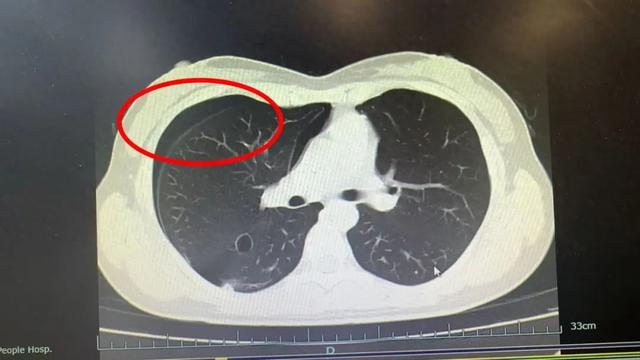

她來到杭州市一醫院瓶窯院區(餘杭三院),呼吸內科主任何立杭接診後,經過詳細問診並結合胸部CT,告訴她是自發性氣胸,便收治入院進行胸腔穿刺抽氣,並置管引流後住院5天好轉出院。

何立杭告訴王小姐因為劇烈運動使肺部壓力瞬間增大,導致肺泡破裂,氣體泄漏進胸腔,壓迫肺部,進而引發氣胸。

而當胸部創傷累及胸壁、肺或氣管時,空氣會經創口進入胸膜腔,導致腔內積氣,這就是常說的氣胸,會影響肺擴張。

何立杭醫師表示,氣胸可分為自發性、外傷性和醫源性三類。像王小姐這樣的情況和平時大家所說「肺都氣炸了」其實就是自發性氣胸。何立杭提醒運動要注意自身情況,不要過於劇烈。